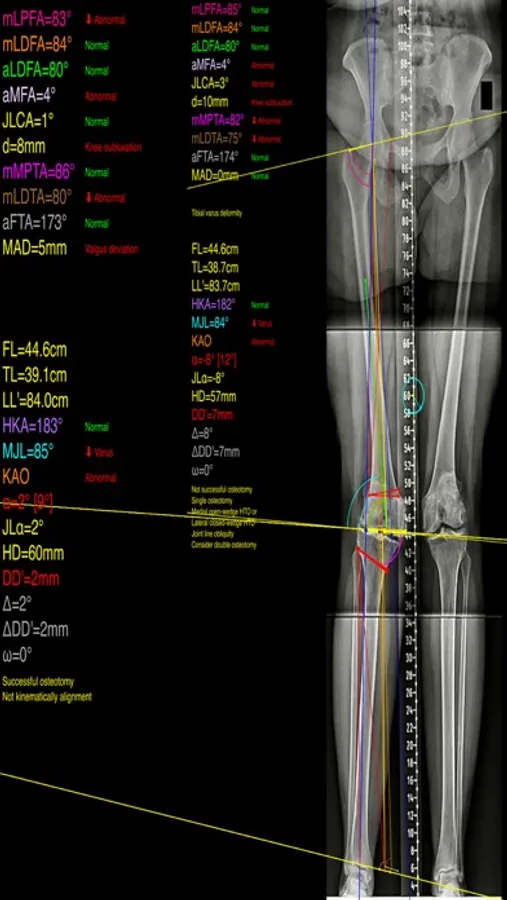

The app assists at preoperative correction planning by calculating :

-the amount of correction preoperatively by calculating the dimension of wedge size , the correction angle and osteotomy gap opening or closing.

-mechanical axis deviation (in mm) MAD, anatomical and mechanical femoral axes angle (aMFA),mechanical lateral proximal femoral angle (mLPFA), mechanical lateral distal femoral angle(mLDFA), joint line convergence angle (JLCA),mechanical medial proximal tibial angle (mMPTA), Mechanical lateral distal tibial angle (mLDTA), Hip Knee Ankle line (HKA) ,Mid joint line (MJL) orientation.

-objectively the deviation or deformity in the frontal plane (varus or valgus) and differentiate the level of deformity (femoral and or tibial origin) and according to measured angles objectively suggest where indicated, medial or lateral, open or closed-wedge distal femur osteotomy or high-tibial osteotomy or double osteotomies and avoiding unwanted obliquity of the joint line

-change the planned mechanical axis to pass at the preferred percentage (Fujisawa point) after evaluation of the residual cartilage thickness left on the involved compartment.

select the location of hinge point of correction osteotomy for planning of varus or valgus corrections

-evaluate in real time the success of intended osteotomy by evaluating the kinematic alignment of the knee (KAO), avoiding residual joint obliquity or malalignment.

-measure the correction angle adjusted due to ligament instability and preoperatively calculate the height of osteotomy gap opening.

-pressing + or - button, one degree of correction is added or subtracted respectively and the second plane of osteotomy emerges and printed in screen real offering real time simulation of the wedge osteotomy in an instant to comprehend in real time what parameters are affected and modify favourably the correction angle. All above mentioned angles and all limp axes are redrawn and updated accordingly for the given new correction angle. The drawn schematic gives the impression of settings act as a whole interchangable interacting unit.

-to combine correction- Biplanar-, at coronal plane and sagittal plane (based on Hernigou 2001 calculations ) on tibia slope and provide the direction of the plane (ω angle) in which the osteotomy (open or closed) should be made ,the height the opening or closing wedge and the correction angle (Δ angle),